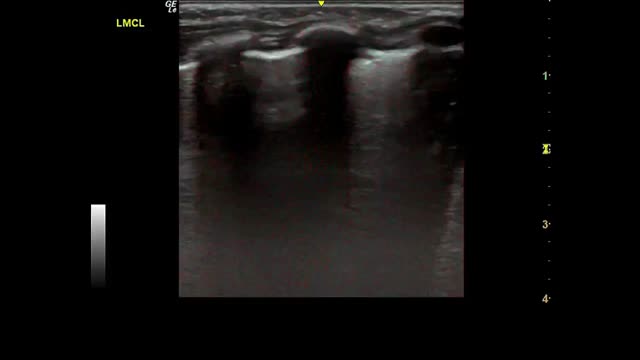

Fig. 2 shows the main findings of the LU imaging described in the study.